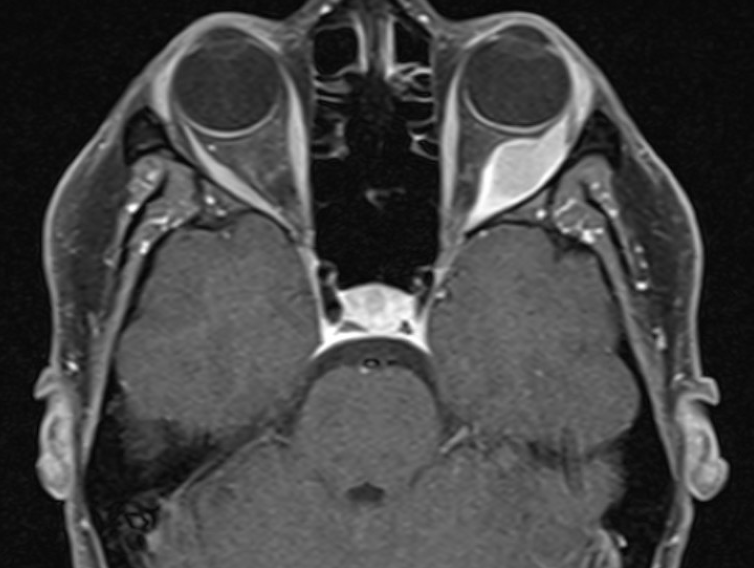

Image 2. Axial MRI of GCT after administration of gadolinium demonstrating avid peripheral enhancement. Image provided by Dr. William Evans MD.